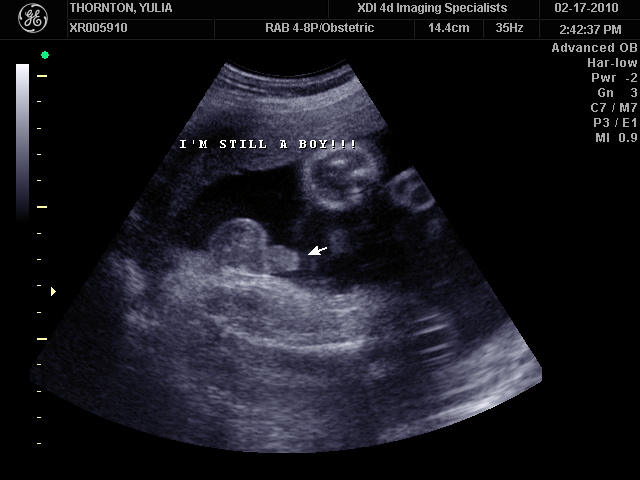

Ну ладно, тогда и я нашего писюна покажу  Надеюсь, Джеффри на меня не обидится Вот это в 23 недели: (там оборудование переключалось из режима 3Д в обычный 2Д)

А это в 30 недель